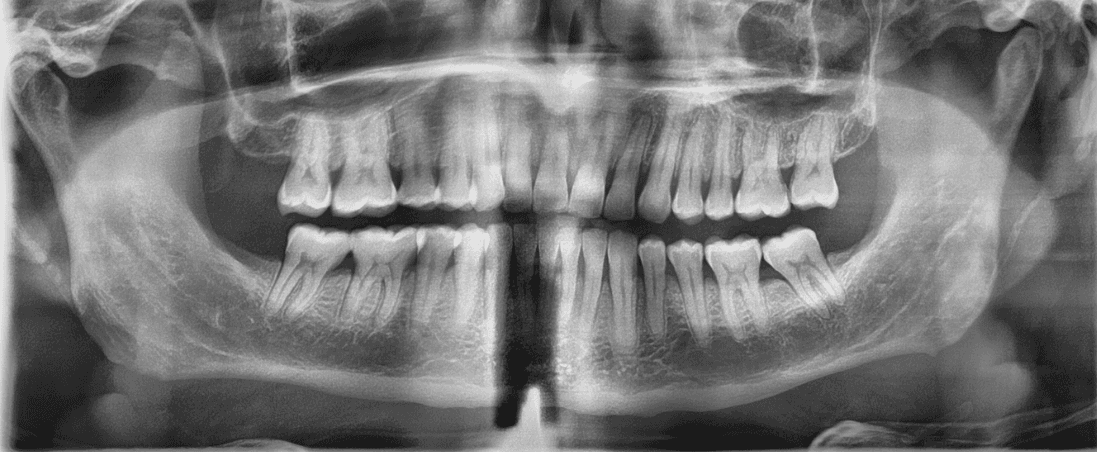

Final results

X-RAYS